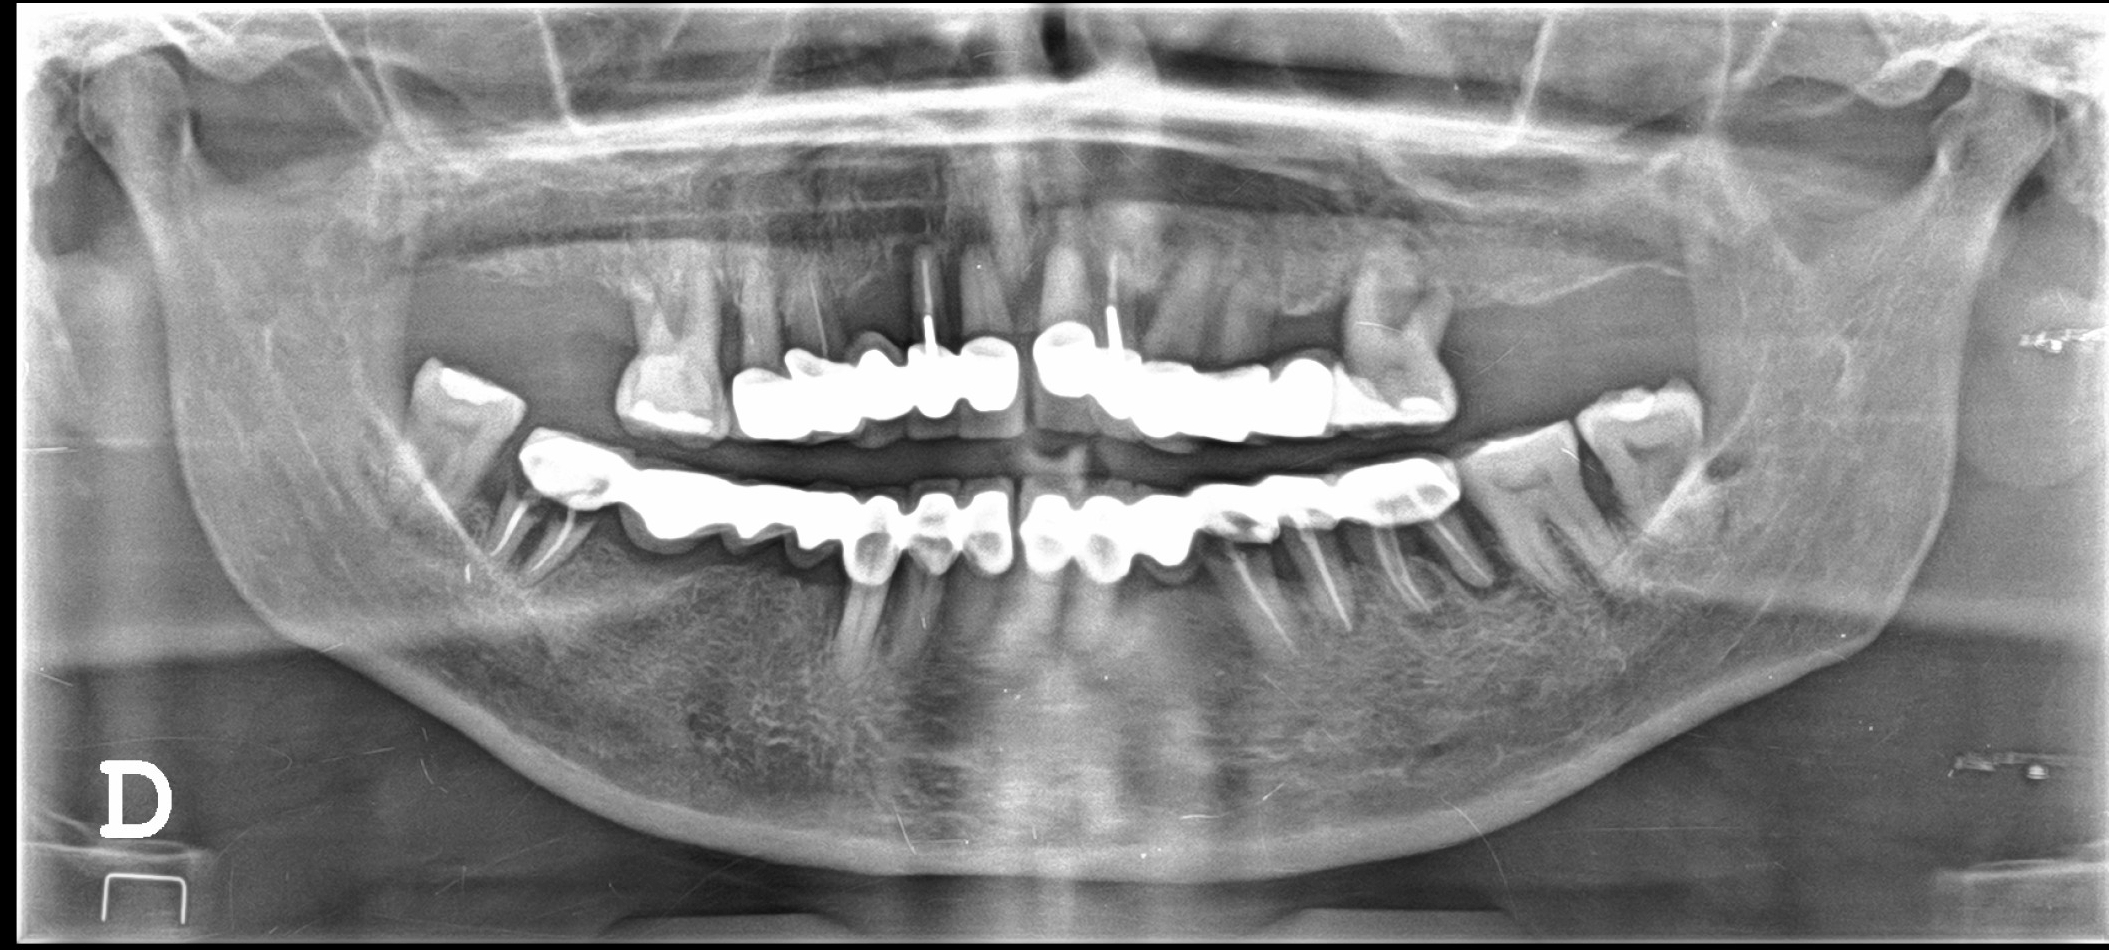

Dental X-rays are more than just tools for diagnosing cavities; they provide a comprehensive view of your oral health status. By allowing dentists to detect problems before they become severe, these images can save patients time, money, and discomfort in the long run. Early detection through modern imaging technology can reveal hidden decay between teeth, bone loss due to gum disease, or even cysts and tumors that are not visible during a standard exam.

- Cavities - Detecting early tooth decay and the need for fillings.

- Root Infections - Identifying abscesses or infections at the tooth's root.

- Gum Disease - Assessing the severity of periodontal issues.

- Impacted Teeth - Revealing teeth that are not properly erupting, such as wisdom teeth.

- Developmental Abnormalities - Monitoring the growth of jaws and teeth in children.

- Tumors - Spotting abnormal growths or cysts within the jawbone.

- Bone Loss - Evaluating the extent of bone loss associated with osteoporosis or other conditions.

- Orthodontic Planning - Aiding in the design of orthodontic treatments and aligners.

- Hidden Dental Structures - Locating hidden canals or sub-surface anomalies.

- Pre-Implant Assessment - Ensuring adequate bone structure for dental implants.

Despite the myths surrounding dental x-rays, they play an integral role in preventative dentistry. X-rays allow dentists to detect issues that are not visible during a standard oral exam. This includes early signs of decay between teeth, problems below the gum line, and changes in bone density that could indicate periodontal disease. By identifying these problems early, fundamental dental treatments can be administered promptly, saving patients from more extensive and costly procedures down the line.